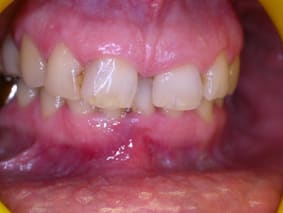

attelle en fibres puis surf puis inj de parocline... j' y croyais pas....et pourtant...

emdogain pour la prochaine étape....